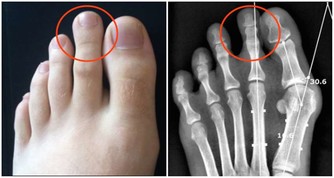

為何泡個腳就猝死 ?該醫院神經外科主任程新富介紹,經檢查發現,劉霞頭部腦血管有動脈瘤突發破裂。腦動脈瘤在未破裂前少有徵兆,很難發現,而一旦破裂,就會突發劇烈頭痛、意識障礙、噁心、嘔吐等癥狀,情況很兇險,致死、致殘率較高。少數特殊的腦血管動脈瘤會有眼瞼下垂、夜間頭痛、行走不穩等早期癥狀。